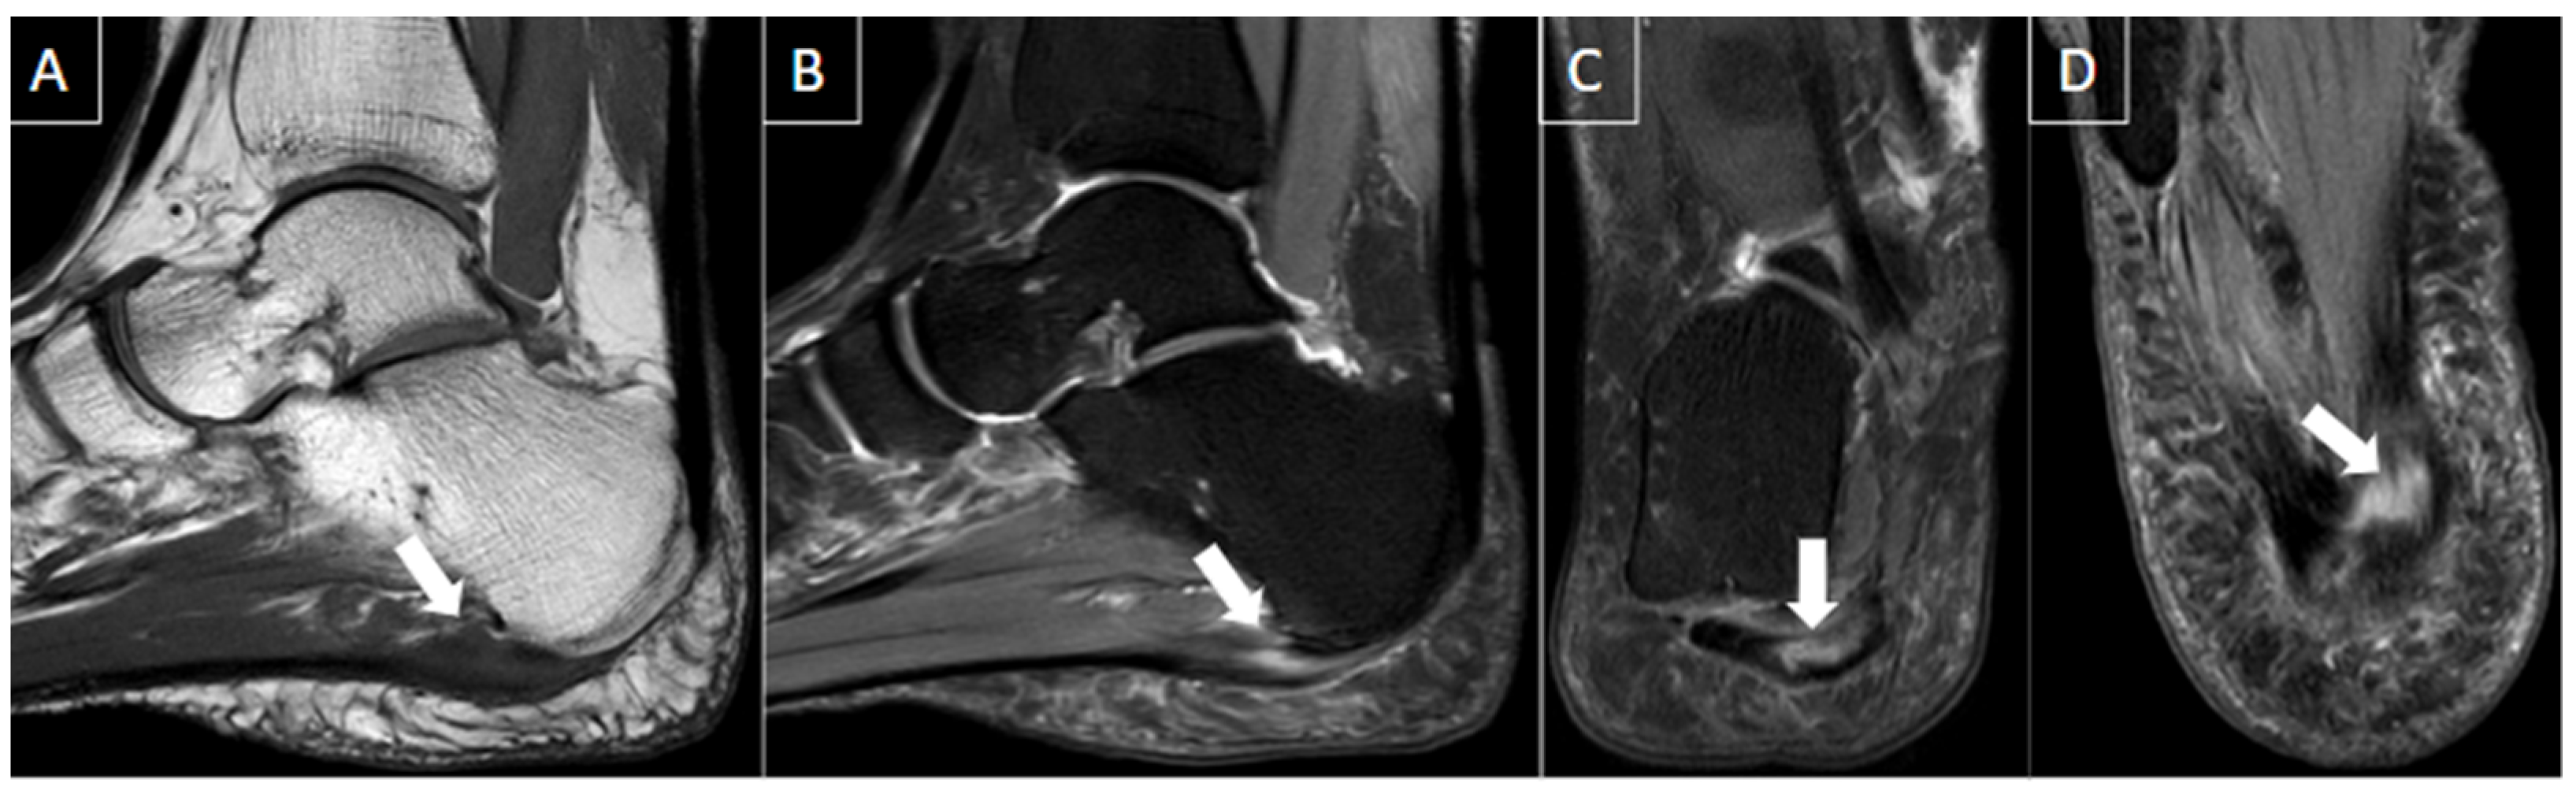

6.4. Plantar Fasciitis

| Plantar fasciitis | Most common cause of unilateral heel pain. | Ultrasound findings include thickening greater than 4.5 mm (the most useful sign), hypoechogenicity of the plantar fascia, and loss of normal fibrillar reflective echotexture. | Hypointense or isointense fascial thickening at calcaneal insertion on T1-weighted images. |